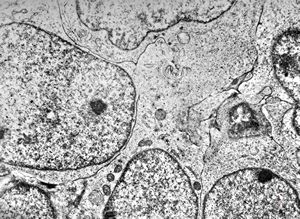

M,13y. | ganglioglioma

M,13y. | ganglioglioma